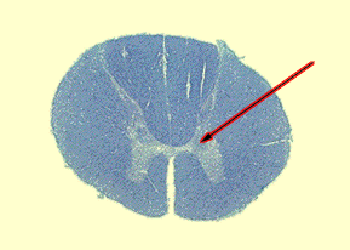

Q9. Identify the nucleus. What type of information is relayed by this nucleus?